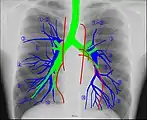

Human chest radiographic anatomy.

Radioanatomy (x-ray anatomy) is anatomy discipline which involves the study of anatomy through the use of radiographic films.[1] The x-ray film represents two-dimensional image of a three-dimensional object due to the summary projection of different anatomical structures onto a planar surface.